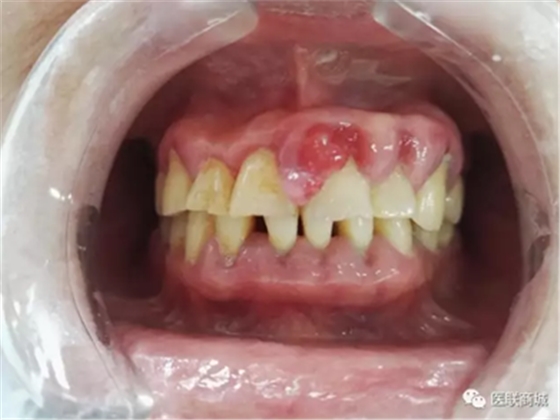

口腔衛(wèi)生狀況較差,牙石(++),軟垢(++),全口牙齦紅腫增生明顯,11、21、22、23牙齦增生明顯,11、21齦乳頭呈菜花樣增生,質(zhì)軟,界清,觸痛(-),易出血,全口PD=5-7mm,下前牙舌側(cè)GR=1-2mm,咬合關(guān)系基本正常,未見(jiàn)明顯咬合創(chuàng)傷。